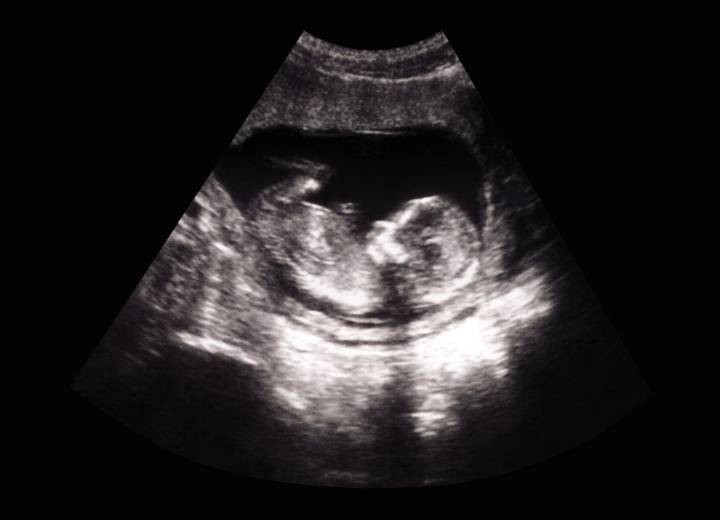

The 32-week scan appeared to show a large hand caressing the head of the unborn baby in the mother’s womb.

The visible answer to her prayers happened to Amanda Foster , 33, who was eight months pregnant with a boy.

She shared her story earlier this year, and she has “asked the Lord repeatedly to please keep his hand on my baby” before every appointment after he was diagnosed with a heart condition early in the pregnancy.